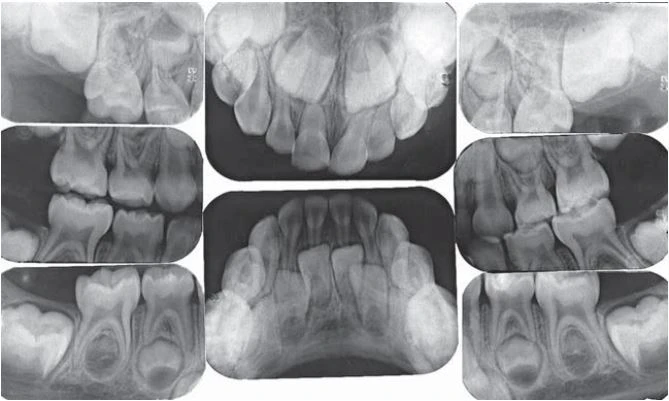

Chụp phim cho trẻ em là một vấn đề khó. Mặc dù nguyên tắc chụp phim quanh chóp cho trẻ và người lớn là như nhau nhưng trẻ lại có cấu trúc giải phẫu nhỏ và khó kiểm soát được hành vi của trẻ. Cung hàm nhỏ hơn đòi hỏi receptor quanh chóp nhỏ hơn. Khẩu cái và sàn miệng cạn đòi hỏi thay đổi việc đặt receptor.

Phim X quang răng sữa bao gồm hai phim mặt phai răng trước, bốn phim quanh chóp răng sau và hai phim cánh cắn